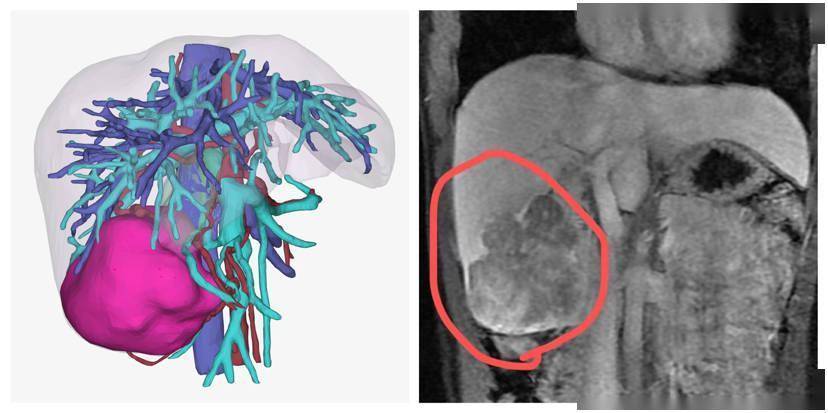

三维重建和MRI影像图片

磁共振扫描结果:肝右叶巨大肿块,周围散在结节状病灶

幸好,小黎身体状况不错,肿瘤没有侵犯临近器官,也没有远处转移,完全可以通过手术切除。经过术前检查和周密计划,何谦副主任医师为她做了右半肝切除手术,用时约3小时,手术顺利。术后病理确诊为肝细胞性肝癌。